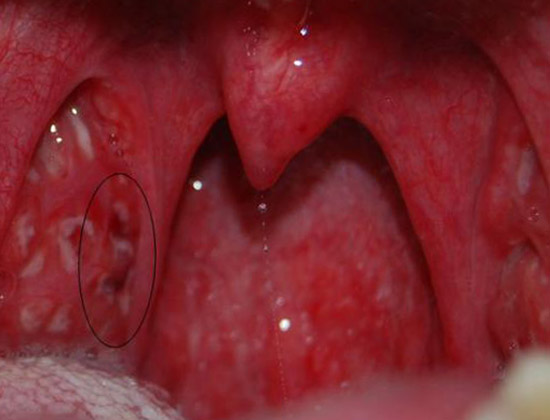

Рис. 2. На фото хронічний тонзиліт. У наявності основні ознаки захворювання, в лакунах видно гній і гнійні пробки.

При хронічному тонзиліті накопичився гній в лакунах може бути рідким або густим. При огляді відзначається наявність гнійних пробок в лакунах. Гній в лакунах є причиною неприємного гнильного запаху з рота, що є важливою ознакою хронічного тонзиліту.

Вміст лакун і крипт мигдаликів

Наявність гною в лакунах і повторюваність ангін протягом року є достовірними ознаками хронічного тонзиліту, які самі по собі мають великою вірогідністю.